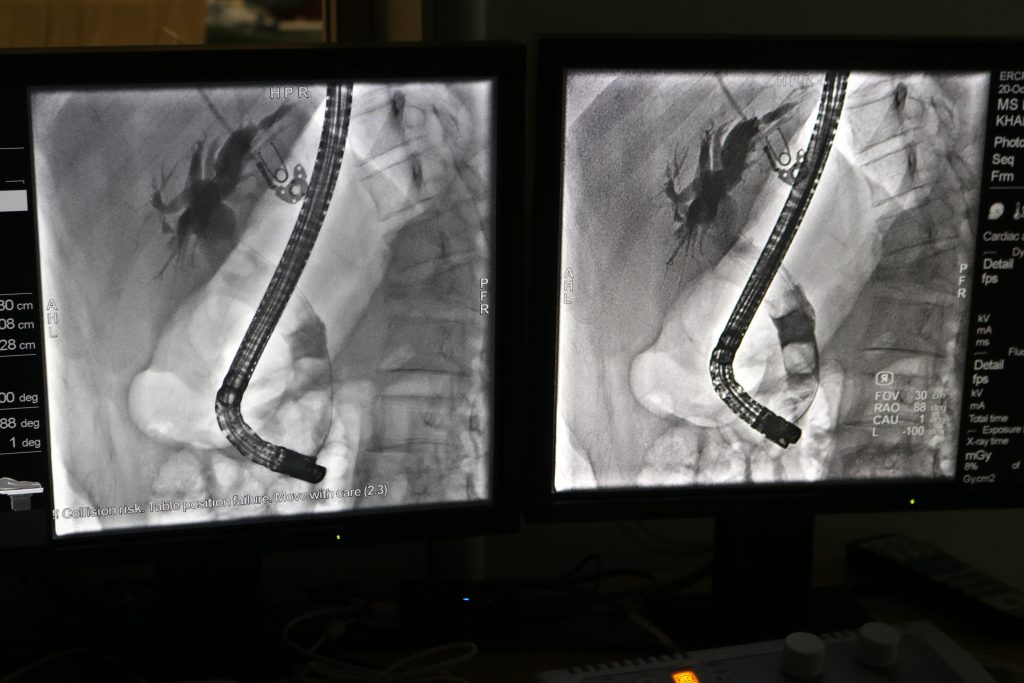

ການເອົາໜິ້ວອອກຈາກທໍ່ສົ່ງນ້ຳບີ ດ້ວຍເຕັກນິກທີ່ທັນສະໄໝ ຜ່ານກ້ອງສ່ອງ ຮູບແບບ ERCP (Endoscopic Retrograde Cholangiopancreatoscopy).

ໃນປັດຈຸບັນ, ການປິ່ນປົວພະຍາດດັ່ງກ່າວມີການພັດທະນາຂຶ້ນ ໂດຍການນຳໃຊ້ອຸປະກອນການແພດ ແລະ ເຕັກນິກທີ່ທັນສະໄໝ ຮູບແບບ ERCP (Endoscopic Retrograde Cholangiopancreatoscopy), ໃນວັນທີ 20 ຕຸລາ 2025 ທີມງານທາງດ້ານວິຊາການ ຂອງໂຮງໝໍມະໂຫສົດ ໄດ້ມີການເຄື່ອໄຫວກິດຈະກຳ ການປິ່ນປົວຄົນເຈັບທີ່ເປັນພະຍາດໜິ້ວທໍ່ນ້ຳບີ ຈຳນວນ 05 ກໍລະນີ, ໂດຍນຳໃຊ້ເຕັກນິກໃໝ່ດ້ວຍການຄີບໜິ້ວອອກຈາກທາງເດີນທໍ່ນ້ຳບີຜ່ານກ້ອງສ່ອງ. ຜົນດີຂອງການປິ່ນປົວດັ່ງກ່າວແມ່ນ ໃຊ້ເວລາ 30-60 ນາທີ, ຊ່ວຍຫຼຸດຜ່ອນການເຈັບປວດກ່ອນການຜ່າຕັດ, ບໍ່ມີບາດແຜ, ຫຼຸດຜ່ອນການເສຍເລືອດ, ອັດຕາການຕິດເຊື້ອໜ້ອຍລົງ, ນອນໂຮງໝໍໜ້ອຍມື້ຟື້ນໂຕໄດ້ໄວ ແລະ ເຊິ່ງເຮັດໃຫ້ຜູ້ມາຮັບບໍລິການເພິ່ງພໍໃຈ.